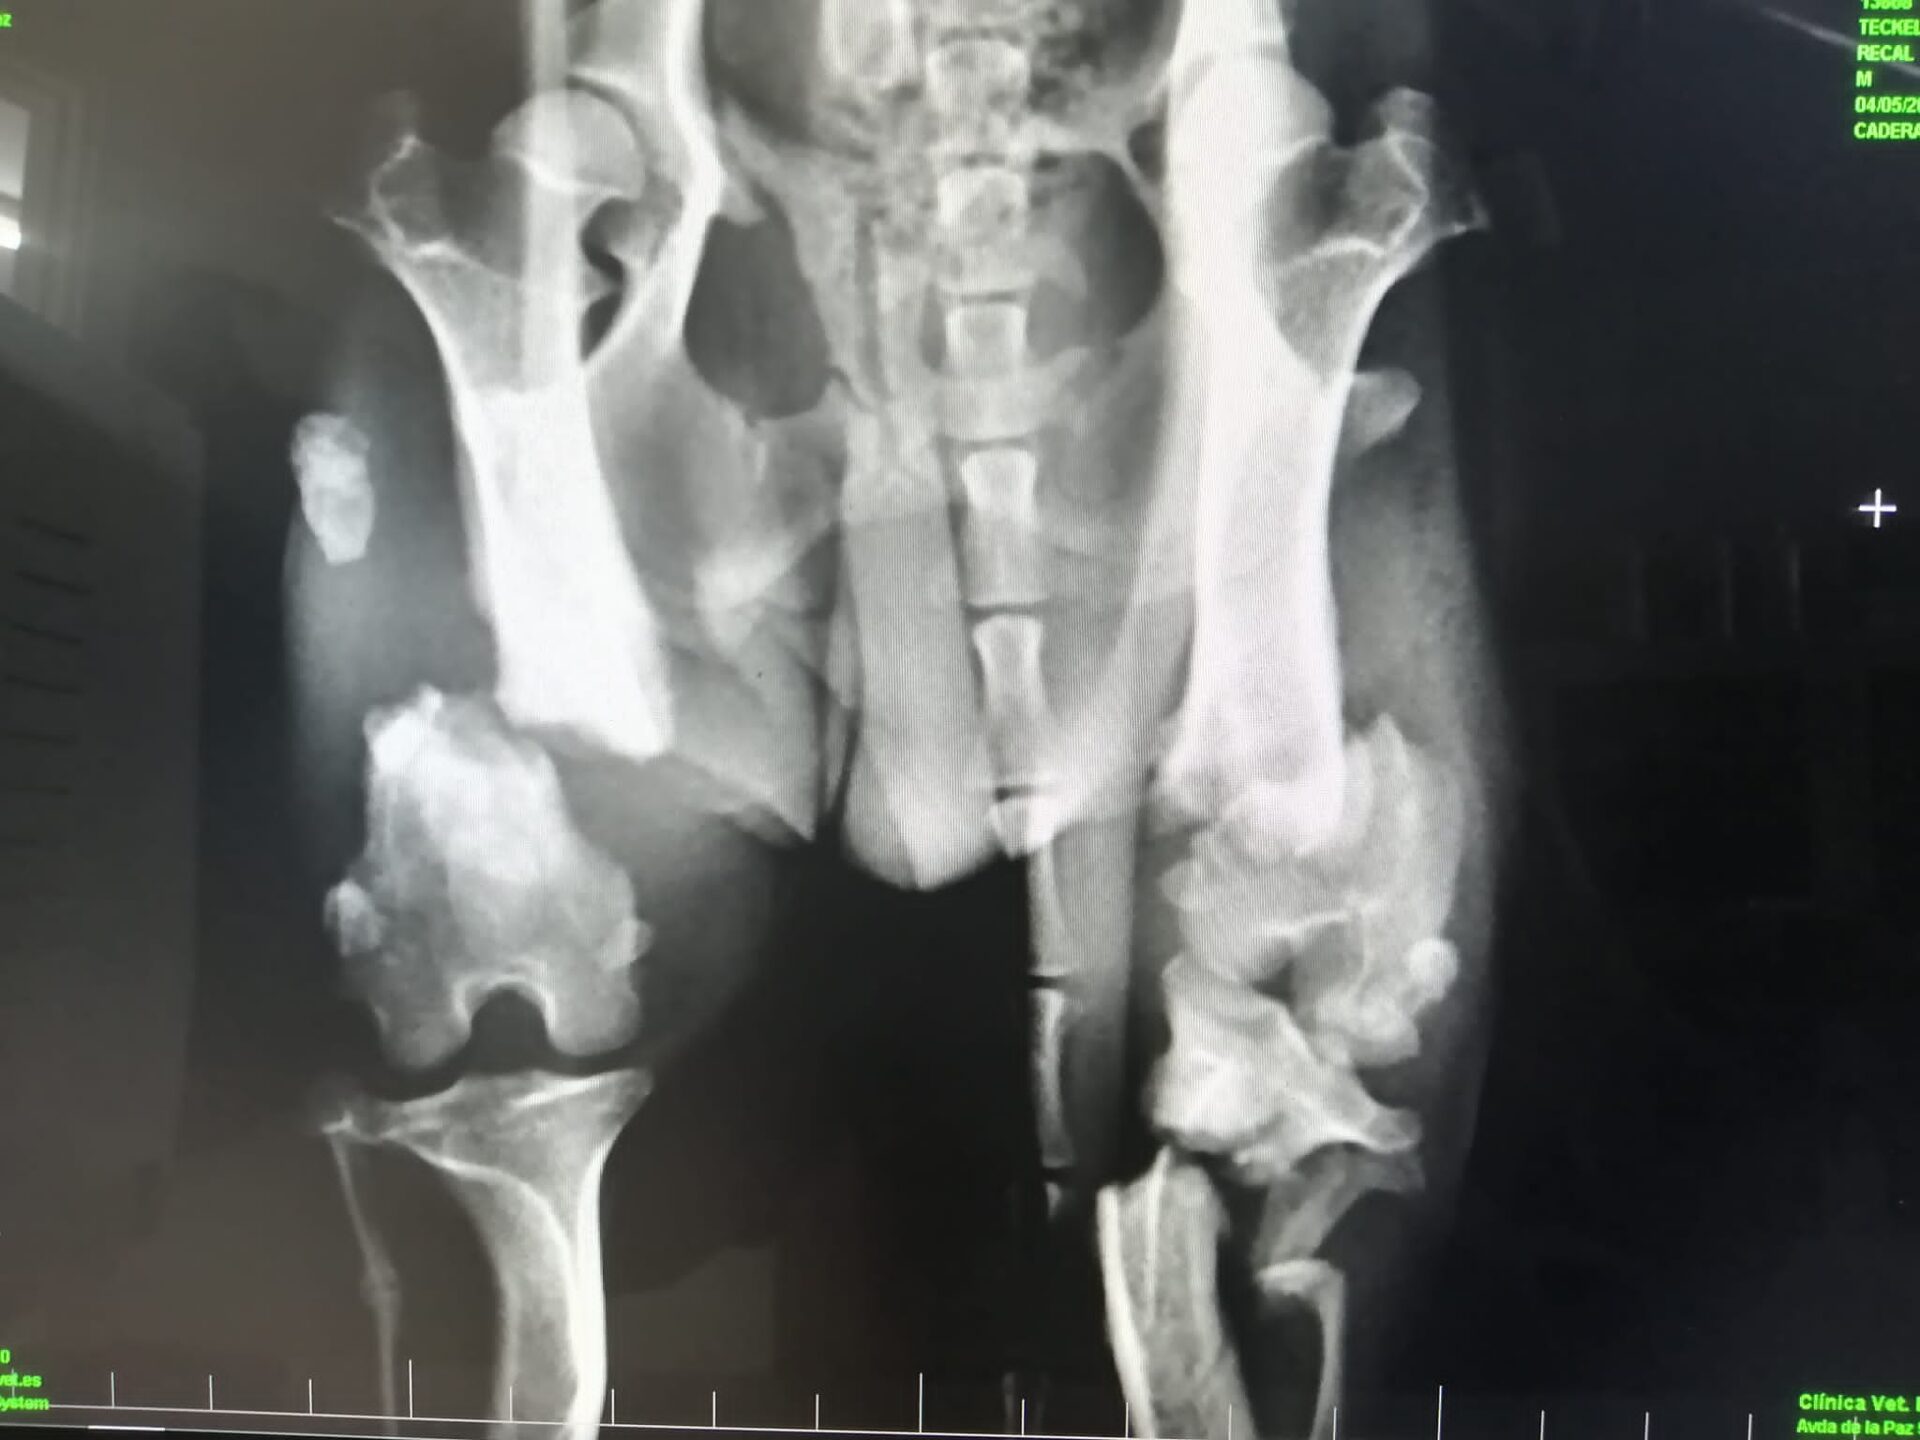

Ihr erinnert euch an Elvis, den jungen völlig abgemagerten Dackel, der mit zwei gebrochenen Hinterläufen gefunden wurde? In dem Zustand hätte Elvis in Spanien keine Chance gehabt und so haben wir uns entschlossen, ihn möglichst schnell operieren zu lassen.

Röntgenbild Elvis vor der OP